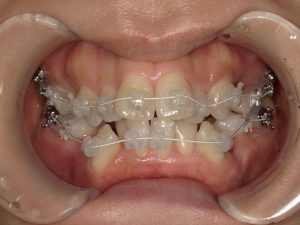

- 主な使用装置

- マルチブラケット装置(+ホワイトワイヤー)、リンガルアーチ、アンカースクリュー

治療中の様子(マルチブラケット装置+ホワイトワイヤー)